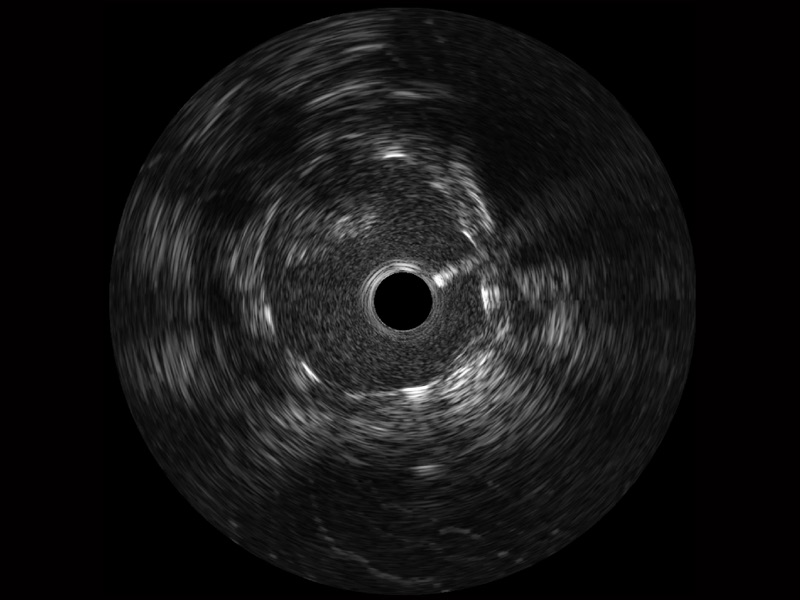

银河集团官网宽频IVUS图像

对比传统IVUS导管成像,银河集团官网宽频IVUS图像的近场支架梁显影更细腻,远场中膜外血管仍清晰可辨,兼顾远中近,兼顾分辨力与穿透深度